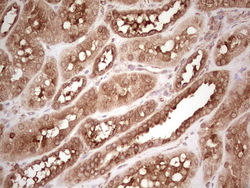

- Experimental details

- Immunohistochemical staining of paraffin-embedded Human colon tissue within the normal limits using anti-WIBG mouse monoclonal antibody. (Heat-induced epitope retrieval by 1 mM EDTA in 10mM Tris, pH8.5, 120C for 3min, TA806496)

- Validation comment

- IHC